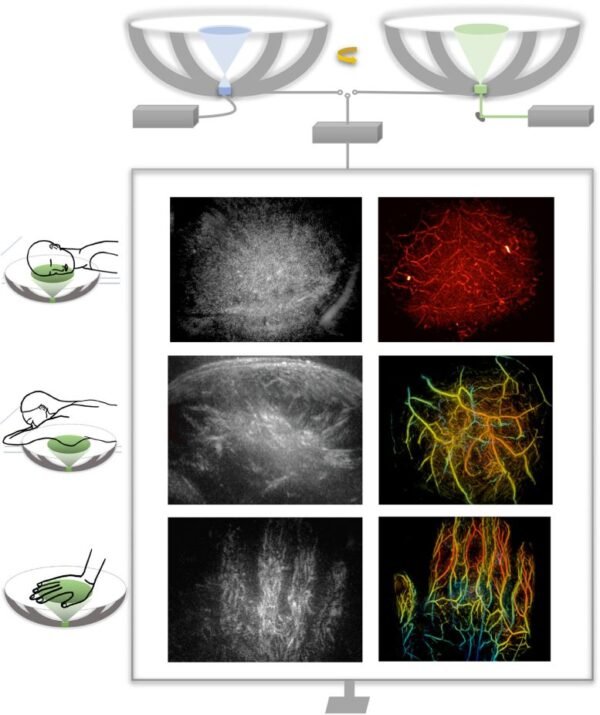

RUS-PAT metodas sujungia ultragarsinę tomografiją su fotoakustika, leidžiant matyti spalvotas 3D kraujagyslių ir audinių struktūras.